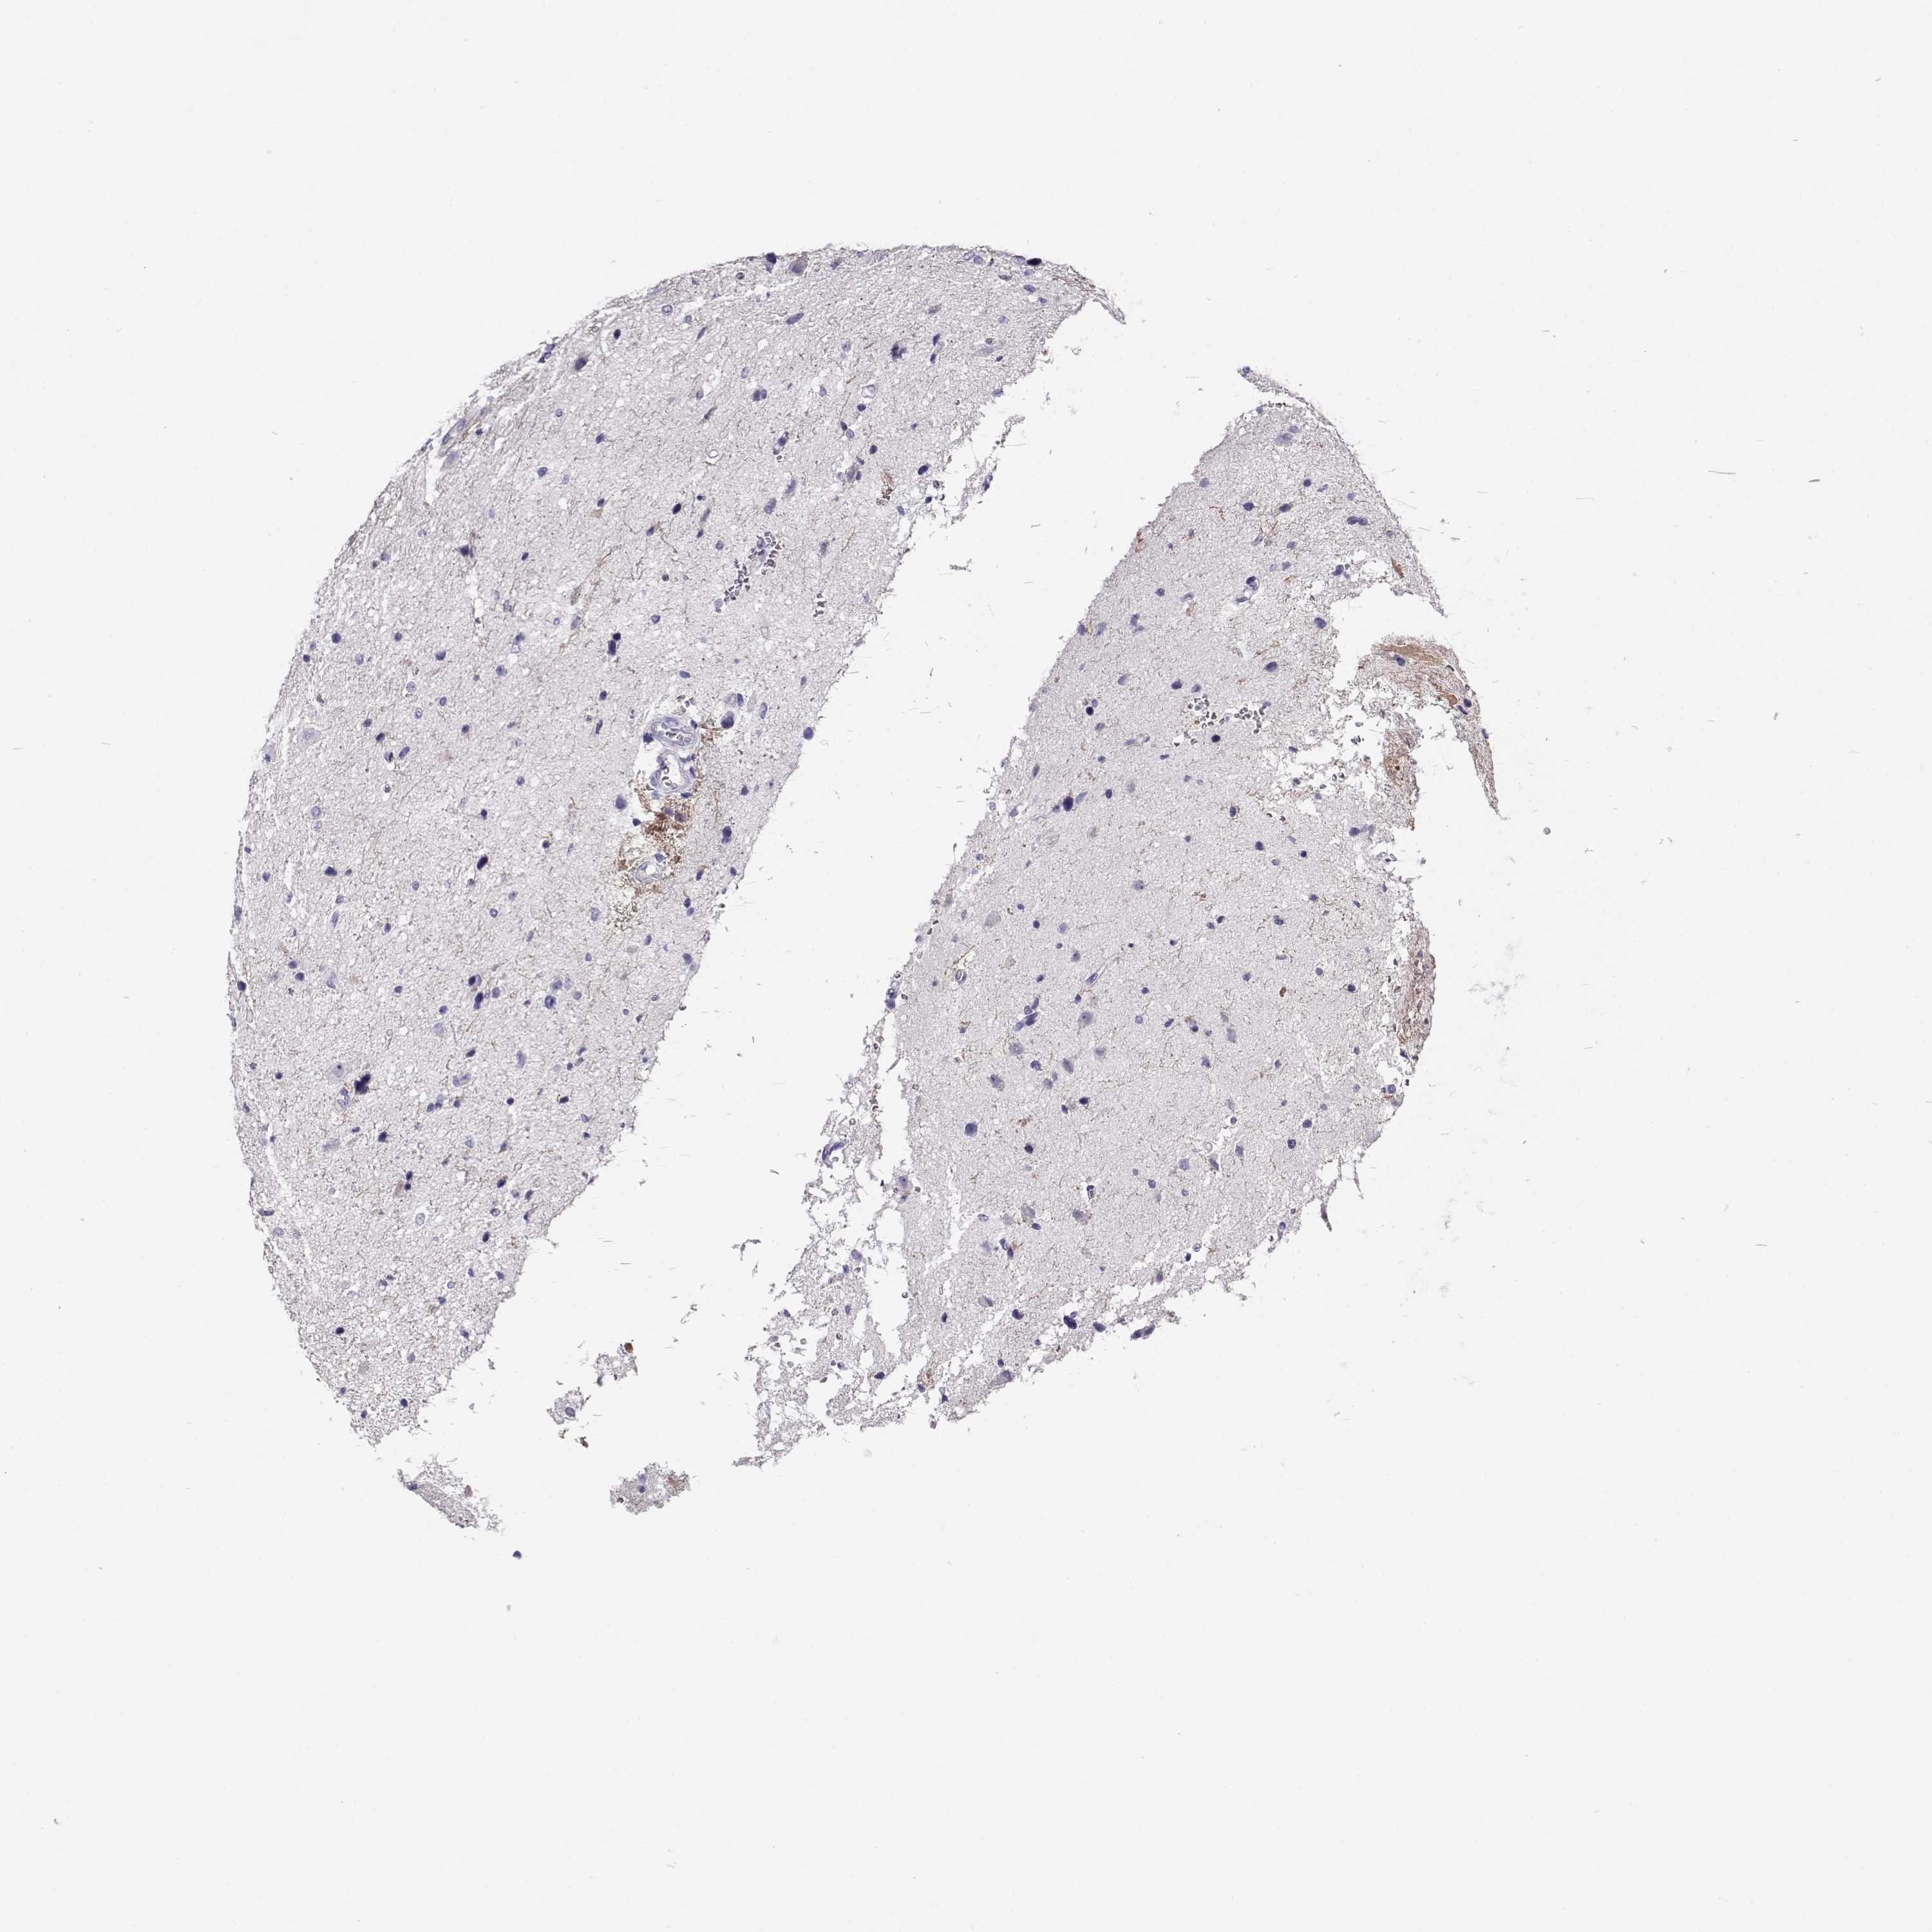

GLIOMA - Protein expressioni

A mouse-over function shows sample information and annotation data. Click on an image to view it in a full screen mode. Samples can be filtered based on level of antibody staining by selecting one or several of the following categories: high, medium, low and not detected. The assay and annotation is described here.

Note that samples used for immunohistochemistry by the Human Protein Atlas do not correspond to samples in the TCGA dataset.

Antibody stainingi

Antibody staining in the annotated cell types in the current human tissue is reported as not detected, low, medium, or high, based on conventional immunohistochemistry profiling in selected tissues. This score is based on the combination of the staining intensity and fraction of stained cells.

Each image is clickable and will lead to virtual microscopy that enables deeper exploration of all samples and also displays staining intensity scores, fraction scores and subcellular localization as well as patient and tissue information for each sample.

Antibody HPA062736

Staining

High

Medium

Low

Not detected

Intensity

Strong

Moderate

Weak

Negative

Quantity

>75%

75%-25%

<25%

None

Location

Nuclear

Cytoplasmic/membranous

Cytoplasmic/membranous,nuclear

Glioma, malignant, Low grade

Glioma, malignant, High grade